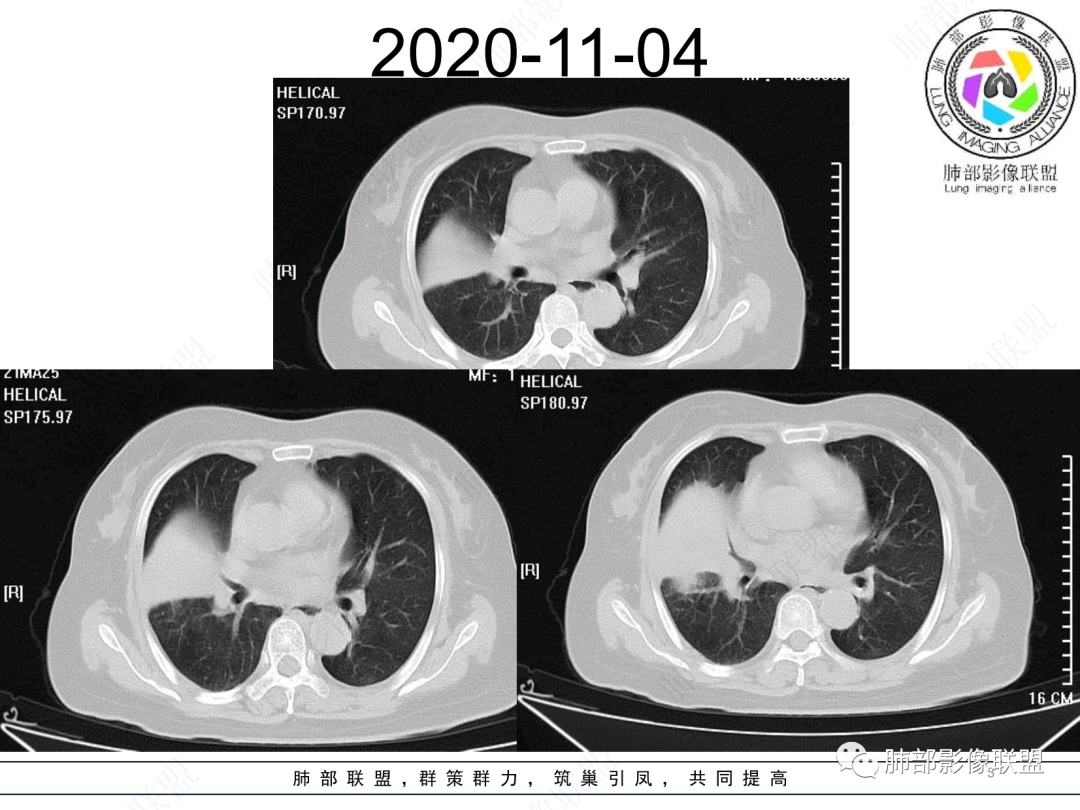

右肺中叶大片实变,内见大片的坏死,中叶外侧段支气管阻塞,相邻胸膜增厚,间隔约四个月后复查,发现低密度坏死内可见气泡影,老年人,反复迁延不愈的病变要考虑恶性,首先考虑腺癌伴感染。鉴别慢性脓肿。

老年女性,慢性病史,炎性指标稍高,肿标正常,右中下肺大片实变,跨叶生长,边界清,收缩力差,膨隆生长为主,支气管杵状截断,均匀强化,其内坏死边界清,可见悬浮气泡,整体观察,病灶膨隆生长为主,邻近肺野无播散灶,形态单一,尽管慢性病史,影像不支持OP和TB,支气管截断呈杵状,肿标正常,均匀强化,虽是高龄患者,诊断恶性肿瘤有点牵强,综和分析,首选炎性病变放线菌感染,其次考虑低度恶性占位炎机母。

这个病灶中叶、下叶都有

坏死腔是连通的

这个支气管局部堵了,但是远端支气管走形自然,腔内粘液栓

这个病例,看长轴、形态,首先跨叶,里面的坏死腔,它是相通的,就是跨中叶及前基底段。

看中叶外侧段的病变,我观察到支气管与坏死腔相通的,支气管这种堵塞就不踏实了,假如是腔内的病变,就不太支持。

然后中叶与下叶的坏死腔病灶是相通的,病灶是跨叶的,胸膜糊墙为主。

我要看一下下叶。还想重建一下,就是按照我自己理解的长轴去重建出这个病灶的整体形态,我当时一看,好像侧向融合的病灶。侧向融合的病灶考虑慢性炎性病变的,有几种,这样大片的病灶,常规都考虑特殊感染多一些,比如隐球,放线菌,奴卡等,都可以这样的改变。